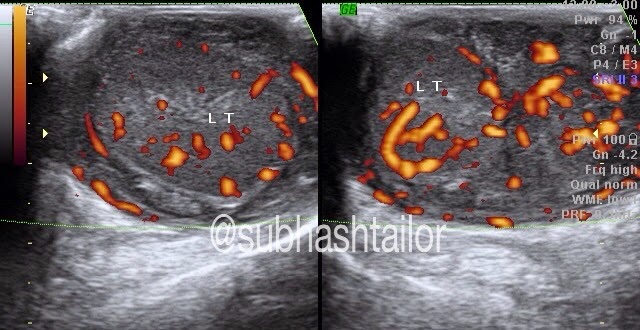

Fig 2- Left intrarenal arterial doppler with similar tradus-parvus flow pattern

not be clearly scanned. However in this case study a low velocity low resistance tardus -parvus waveform is seen in both sided

intrarenal renal arteries [fig 1 & 2 ]. The parvus tardus waveform of the renal

artery is characterized by a slow rise of peak velocity distal to the stenosis,

prolonged acceleration time and reduction of ipsilateral resistive index. This suggested